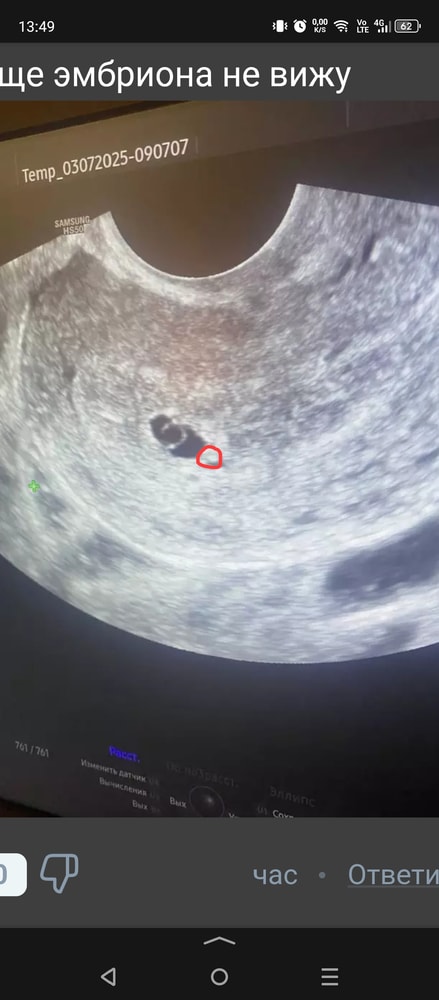

Юлия *, есть еще фото. Я тут вообще эмбриона не вижу

может вот???